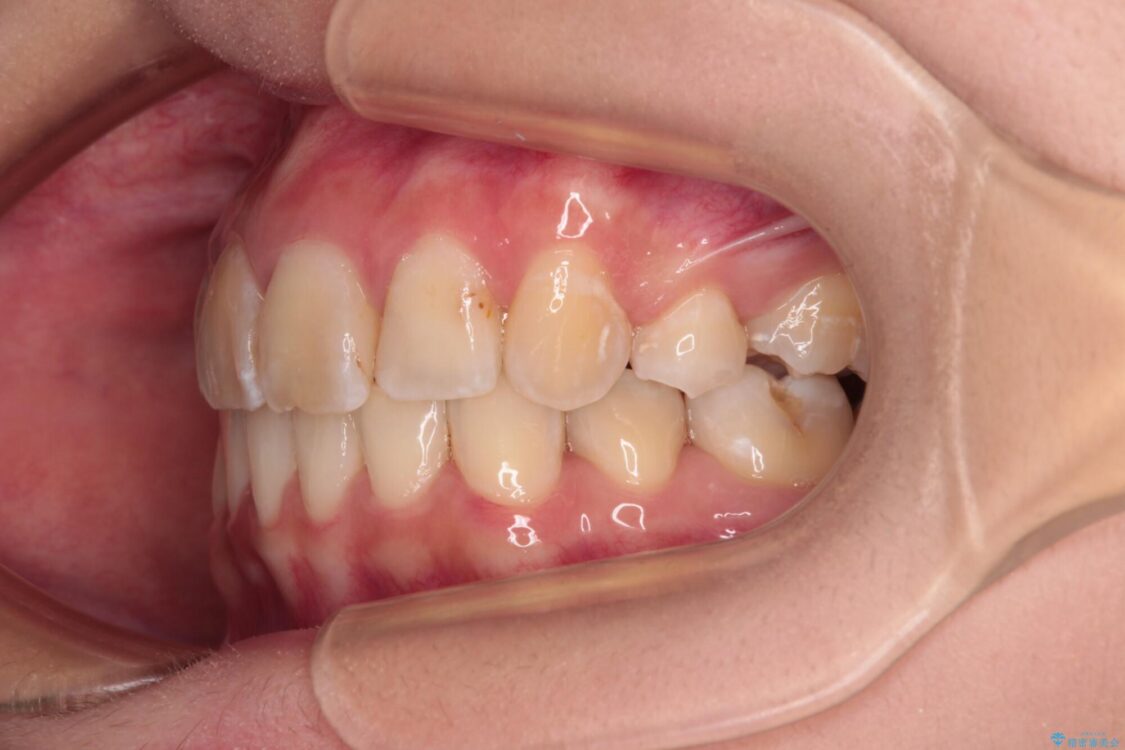

内側に倒れ込んだ歯や下の前歯が隠れてしまうほどの咬み合わせを改善したいとのことで来院された患者様です。

下顎の叢生を解消するために抜歯が必要であり、奥歯の咬み合わせや口元の印象から、上顎も同様に抜歯と判断し、上下左右の第1小臼歯4本抜歯してワイヤー装置にて矯正治療を行うこととしました。

咬み合わせが深く、そのままでは上顎の抜歯スペースが閉じきらない可能性があったため、治療初期から深い咬み合わせを改善させるように試みました。

治療後

• デコボコと深い咬み合わせ ワイヤー装置での抜歯矯正 治療後画像